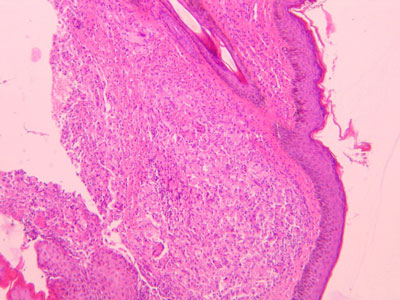

Photo 8 : histologie du nodule

Photo 9 : histologie du nodule vue rapprochée de la zone granulomateuse

On décrit classiquement un épiderme acanthosique, qui peut être ulcéré. Le derme voire la zone sous dermique profonde est atteint. Le derme est le siège d’une réaction pyogranulomateuse mais plus souvent granulomateuse diffuse à nodulaire ou sont présents de nombreux organismes entiers ou dégradés dans et autour des macrophages. Le centre des lésions nodulaires peut être nécrotique.

Deux colorations particulières permettent de mieux repérer les Protothecas: la coloration à l’acide périodique de Schiff (PAS) et celle de Gomori methenamine silver.